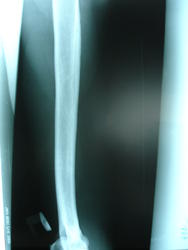

Здравствуйте, уважаемые коллеги прокомментируйте пожалуйста снимки(что это может быть?) 46 лет, муж., появилась болезненность при движении рукой (3 недели назад) и мягкотканный валик по боковой поверхности правой плечевой кости, травму отрицает.

"Мягкотканный валик" может быть сокращенной мышцей вследствие разрыва сухожилия. В кости патологии нет, но может наслаиваться тень гематомы.

На мой взгляд, бугристость как бугристость.

На третьем снимке цепляет  неровность контура, все-таки порекомендовала бы контроль недели через 2-3

Болезненность локализуется на уровне кортикального просветления, травмы не было, кожа не изменена.

Периостальной реакции я не вижу, контур ровный.

уместно ли здесь говорить о "злом" процессе.

Возможно оссифицирующий миозит

Оссифицирующий миозит всё же больше выглядит так:  http://www.radiomed.ru/blogs/andrei-kastarnov/ossifitsiruyushchii-miozit

Что за полоска просветления линейной формы в кортикальном слое плечевой кости?

Надо думать, что "это" норма.

Ну вот, справа в кортикальном слое бегристости плечевой кости полоска просветления есть, а слева - нету. Так , может, справа "не норма"?. Или за счёи проекционного искажения такая разница?

видимо не "докрутили" руку

контроль кортикального расслоения